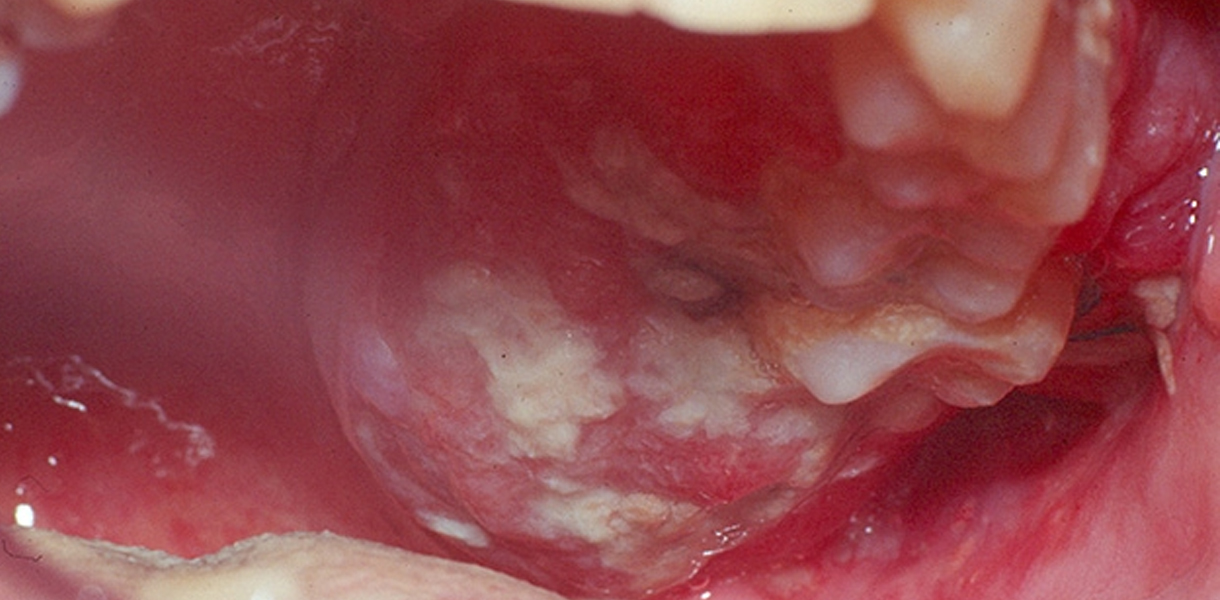

- Lesions of mouth, lips, and tongue